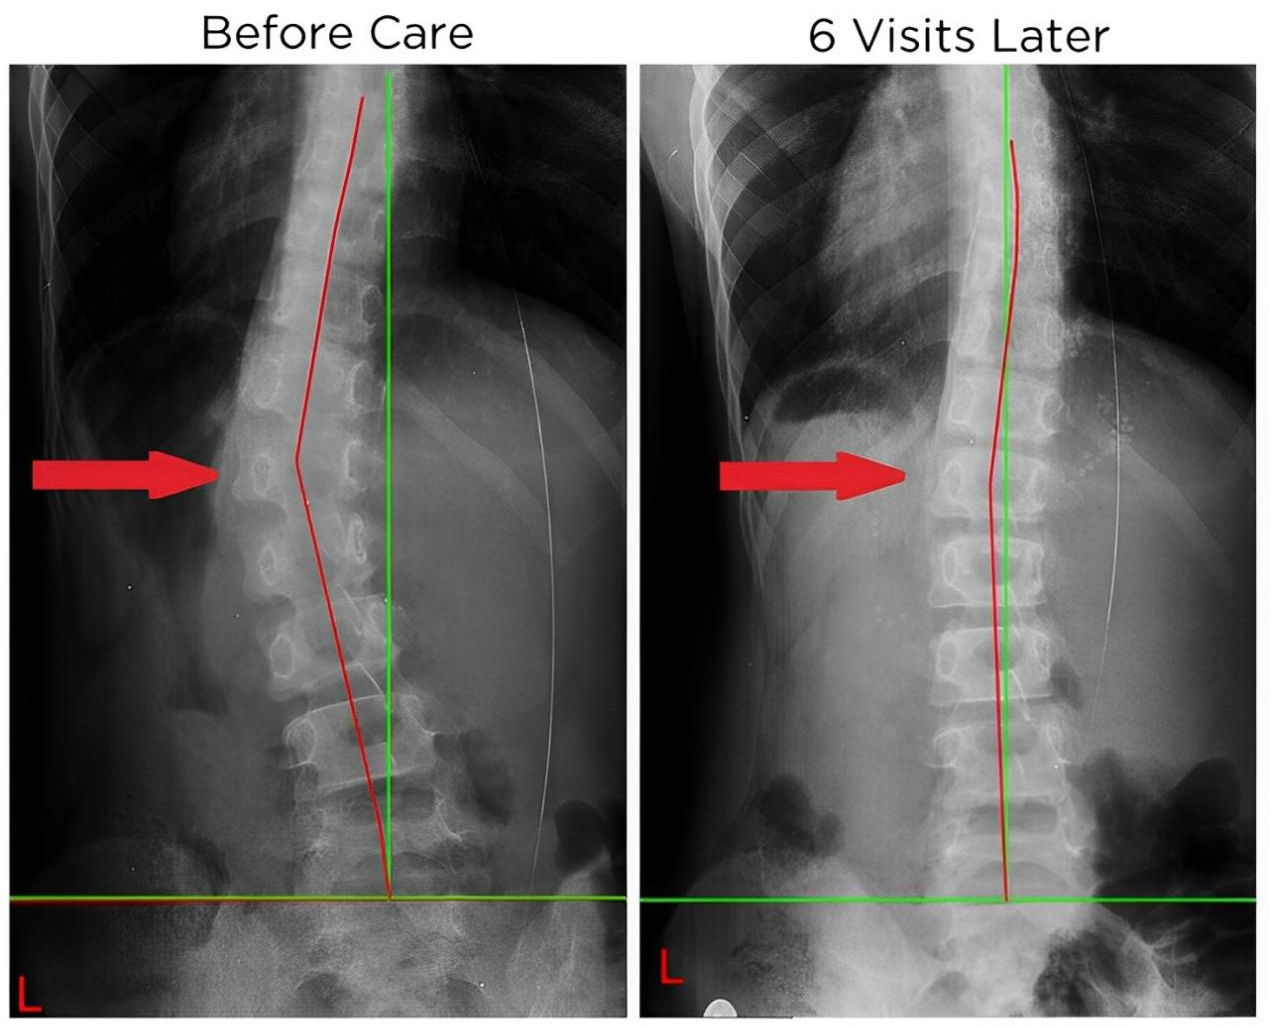

四、 恢復脊椎自然曲度

脊椎整復床的獨特設計能夠幫助恢復脊椎的自然曲度,改善脊椎側(cè)彎和不良姿勢,讓您重獲健康體態(tài)。

五、矯正完和矯正后的對比案例: